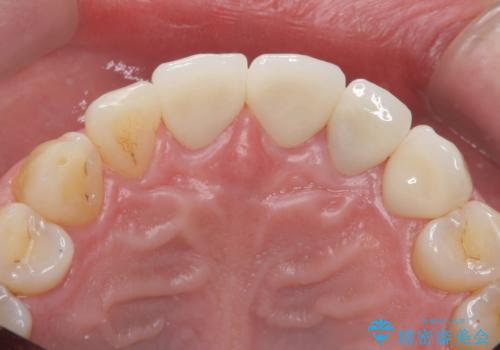

また、左上犬歯の詰め物は途中で脱離し、セラミックでの修復をご希望されたため、一緒に治療しました。

根の治療を行い、ぐらつきに関しては様子を見て連結をするとのお話をさせていただきました。

結果ナイトガードの使用によりぐらつきはだいぶ回復してきたため連結はしていません。

- 81.4万円 内訳:ジルコニアクラウン(スタンダード)11万円×4本 /精密根管治療 前歯、イニシャル 6万円×3本 /ファイバーコア 2万円×3本 /仮歯 1万円×3本/フラットタイプナイトガード 3万円費用は治療当時の料金となります

今後事故の影響でほかの歯の神経が死んでしまったり、状態が変化する可能性があるため経過観察が大事になってきます。